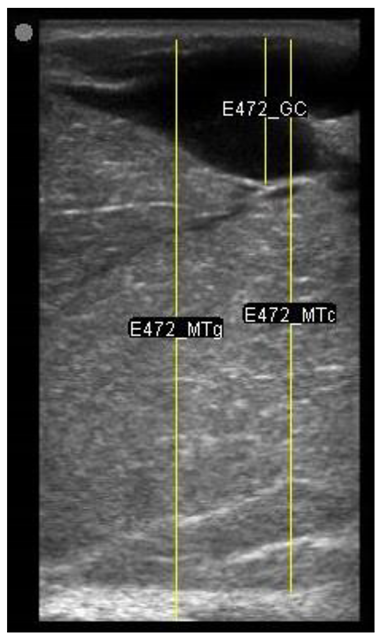

A minimum of three images were taken from each udder half. Images included the gland cistern, mammary parenchyma, putative fat pad and the boundary between the mammary gland and the abdominal wall. One image of suitable resolution per udder half, where all structures were identifiable and present was selected for image processing [27]. Udder halves with an udder palpation score of 4 or 5 (Table 1) at a specific time point (P107, L29 or L100) were considered “abnormal” [23] and were not included in the image selection (heavy: 1 ewe with 1 half and control: 2 ewes with 1 half each).

The image processing was undertaken using ImageJ software [28] as used by Abràmoff et al. [29]. The scales between pixels and millimetres were calculated based on the number of pixels, the scanning depth (mm), and the transducer width (mm) (Figure 4). This method relies on the ability of the operator to interpret and identify lines on the images. To standardize the assessment compartment depth, drawing templates were created for each time point as used by Molenaar et al. [30] and included four representative images from four different yearling ewes with and without the lines drawn for each compartment (Appendix A). The total depth of mammary gland conservative (MTc) was the smallest likely demarcation (abdominal wall) of the mammary gland (Figure 5a), and total depth of the mammary gland generous (MTg) was the largest likely demarcation of the mammary gland visible on the image [30] (Figure 5a). The MTc, MTg, fat pad (FP), parenchyma (PAR), and gland cistern (GC) depths were estimated at the deepest point for each sub-compartment, excluding the skin layers, using the straight tracer (Figure 5a) and were expressed in millimetres.

Figure 5.

(a) Demonstration of delimitations of the mammary total depth conservative (MTc) and generous (MTg), mammary gland cistern (GC), parenchyma (PAR) and the fat pad (FP) and (b) Demonstration of randomly positioning of regions of interest (1, 2, 3) in the parenchyma.

Appendix A. Drawing Templates of Mammary Ultrasound Images in Late Pregnancy, Early Lactation and Weaning in Yearling Ewes

Drawing template of mammary ultrasound images in early lactation (29 days of lactation; L29) in four different yearling ewes.